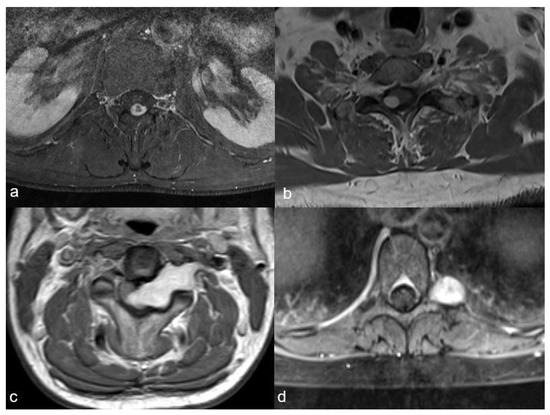

4. Illustrative Case